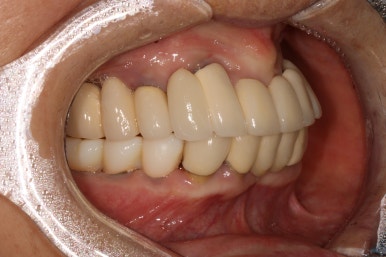

차이를 별로 못느끼실 수 있겠지만, 임플란트 보철물 완성 6개월 후 방문 때 구강내 사진입니다.

감사히도 환자분께서 상당히 깨끗하게 유지하고 계셔서, 잇몸에 염증하나 없이 너~무 보기 좋더라구요.

어금니 좌측

좌우측 측면 사진 비교시, 아래 어금니 임플란트로 깔끔하게 메꿔진 빈 공간이 인상적입니다!